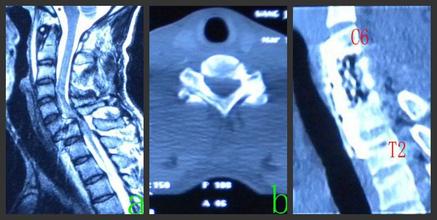

2.頸椎損傷伴椎間盤突出壓迫脊髓者。此種情況多見于頸椎后伸損傷或壓縮損傷,MRI可提供明確診斷。

3.陳舊性頸椎骨折脫位未復(fù)位,或向后成角畸形愈合,脊髓受前方壓迫呈不全癱者。

5.爆裂骨折減壓

爆裂骨折向后移位骨塊的取出方法系將其上下椎間盤切除后,再將骨塊取出。用環(huán)鋸方法將骨折椎體上下椎間盤取出時(shí),由于椎體已骨折,骨折椎體側(cè)的骨柱可能取不完全。于上下椎間盤取出后,剩下中間骨折椎體,以咬骨鉗將其咬除,直至將后移位的骨塊取出,進(jìn)行完全減壓。遺留下的長方形減壓窗,其植骨方法見后述。

6.陳舊性頸椎骨折脫位的減壓

陳舊性骨折脫位壓迫脊髓的范圍,常包括脫位的椎間盤及其下位椎體。因此減壓范圍應(yīng)包括上下椎間盤及壓迫椎體。減壓方法基本同上述。但因?yàn)閮勺刁w后緣不在同一平面,如用同一環(huán)鋸鋸斷不同平面的椎體,有損傷脊髓之虞。故應(yīng)將指示鉆芯貼椎間隙上或下緣打入,分別用環(huán)鋸切除上,下椎體。